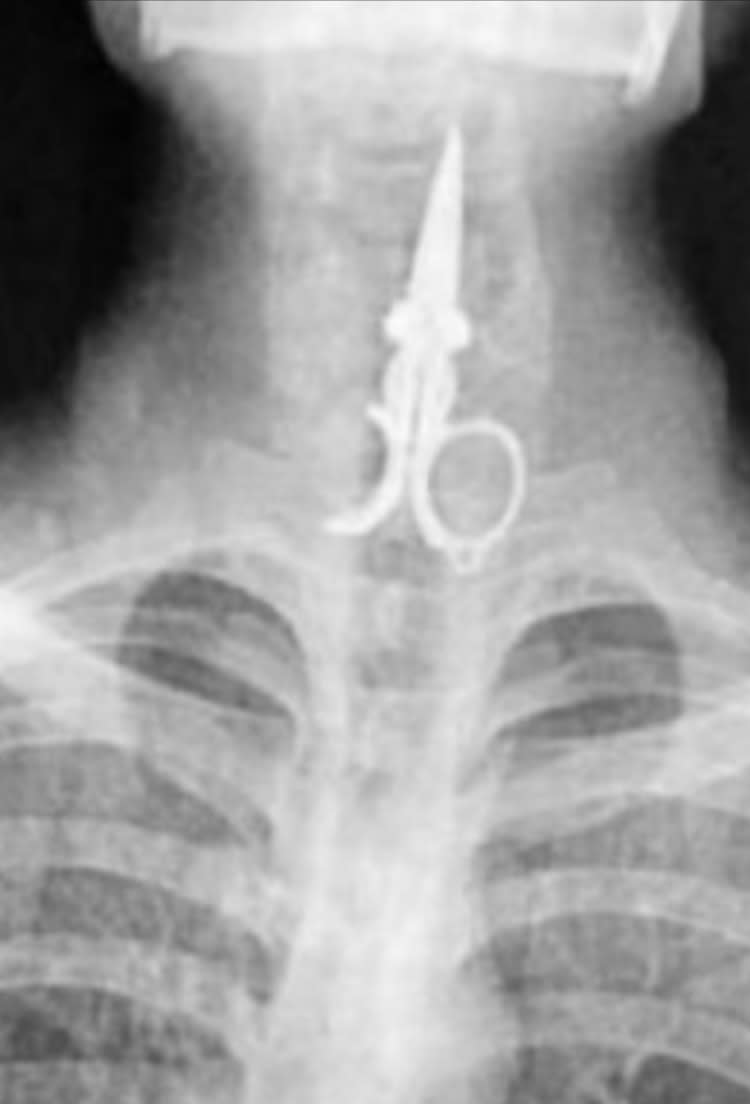

Est ce que c'est du fake ? Paire de ciseaux